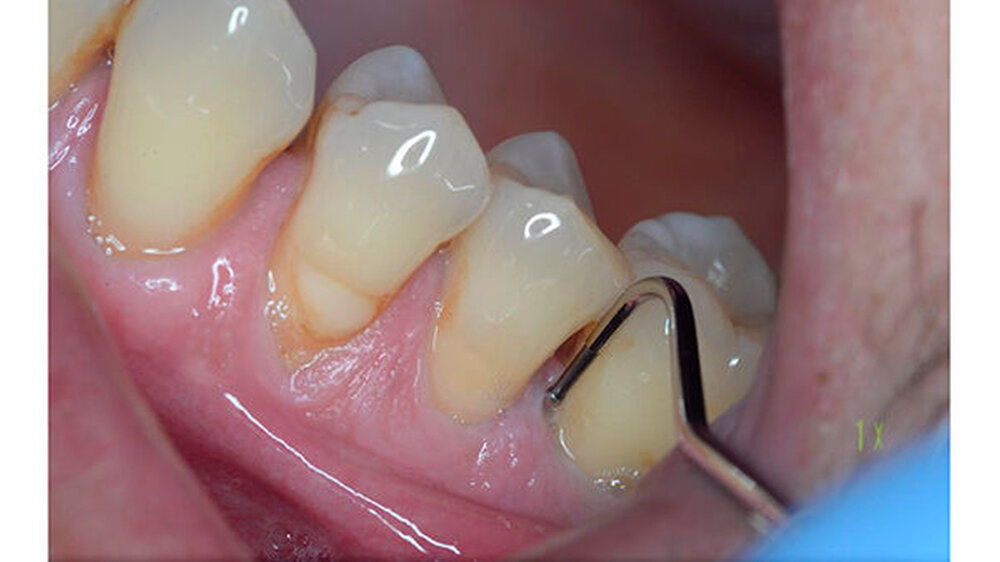

Ein 51-jähriger sportlich muskulöser Patient mit kariesfreiem Gebiss stellte sich zur konsiliarischen Untersuchung vor einer Operation der Kieferhöhle vor. Auf dem OPT imponieren der im Oberkiefer deutlich erkennbare horizontale Höhenverlust mit starker vertikaler Komponente in Regio 15/16 sowie der im Unterkiefer starke vertikale Knochenverlust in Regio 36. Allgemeinerkrankungen oder Medikationen wurden anamnestisch verneint.

Die CT-Aufnahmen zeigen eine deutliche bis zum Orbitaboden heranreichende Totalverschattung der rechten Kieferhöhle. In Höhe des Zahns 16 zeigen sich periradikuläre Rarefikationen als Hinweis auf eine aggressive lokale Parodontitis.